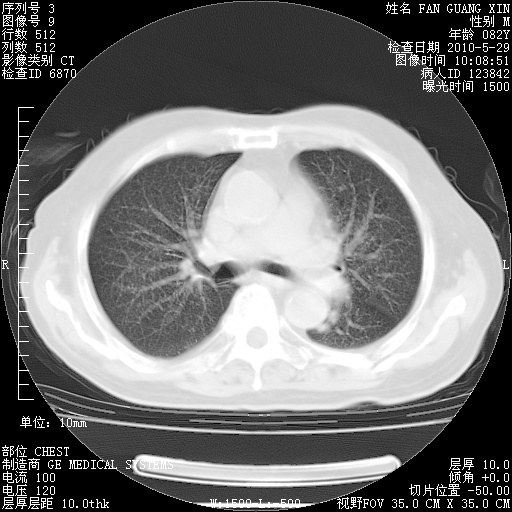

再治疗10天后的肺部CT

阅读此次胸部CT,肺间质渗出性改变较入院时有吸收。目前从体温、白细胞、中性分叶明显增高,肯定存在细菌感染(发生医院感染哦,若无消化道及泌尿系统等感染的依据,肺部感染可能大)。若你院头孢哌酮舒巴坦钠耐药率较高,同意你的方案,若48小时体温仍高,可考虑使用碳青霉稀类抗菌药物,同时可予超声雾化、注意滴数时加大液体量。白蛋白33.30g/L较低哦,需加强营养等支持治疗。